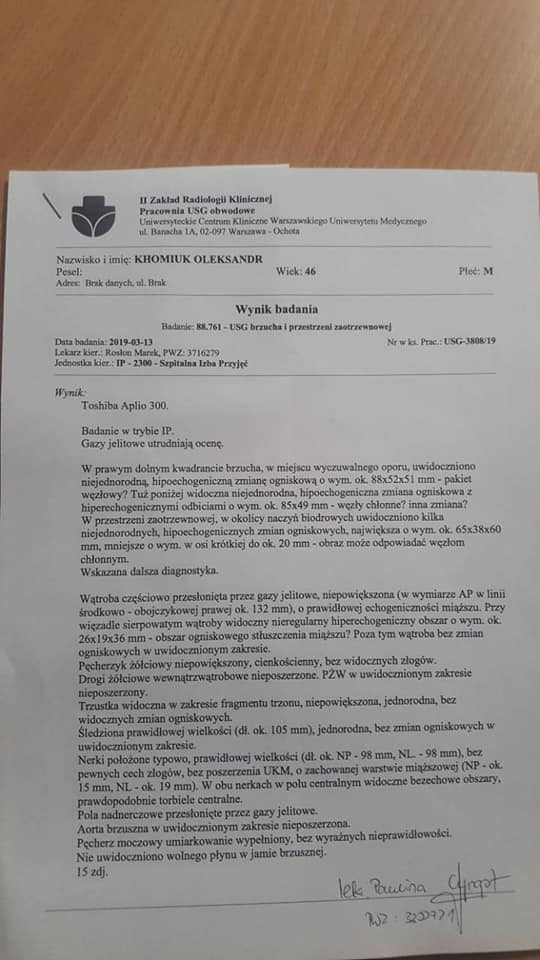

Як повідомили його близькі у Фейсбуці, у нього негоджкінська лімфома великих клітин В, початок 4 стадії.

Наприкінці листопада 2018 року росла гуля біля у пахві. Через три з половиною місяці вона збільшилась і як виявилося, це новоутвореня – злоякісна лімфома...

Як повідомили його близькі у Фейсбуці, у нього негоджкінська лімфома великих клітин В, початок 4 стадії.

Наприкінці листопада 2018 року росла гуля біля у пахві. Через три з половиною місяці вона збільшилась і як виявилося, це новоутвореня – злоякісна лімфома...